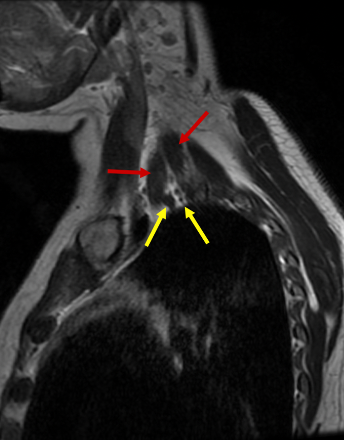

We report a case of a 51-year-old male presented to the neurology clinic with intermittent dizziness, blurred vision, chronic left sided weakness and numbness. Further workup by brain MRI unearthed increased intracranial pressure secondary to impaired CSF drainage. He was previously diagnosed with Arnold Chiari type I malformation for which ventricle-peritoneal shunt (VPS) was performed in 1994 (Figure 1).